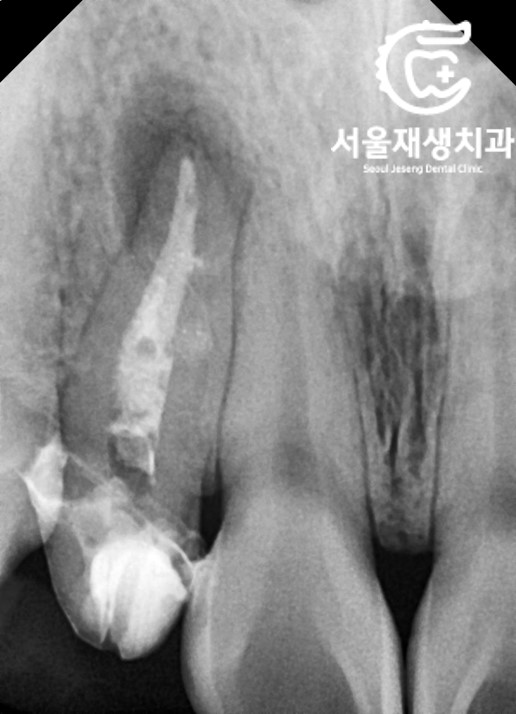

재신경치료 시작~

이전 치료에서 포스트

(=뿌리와 머리를 연결해주는 지지대)가

있었지만,

어렵지 않게 제거하고

뿌리 끝까지 꼼꼼히 청소하였습니다.